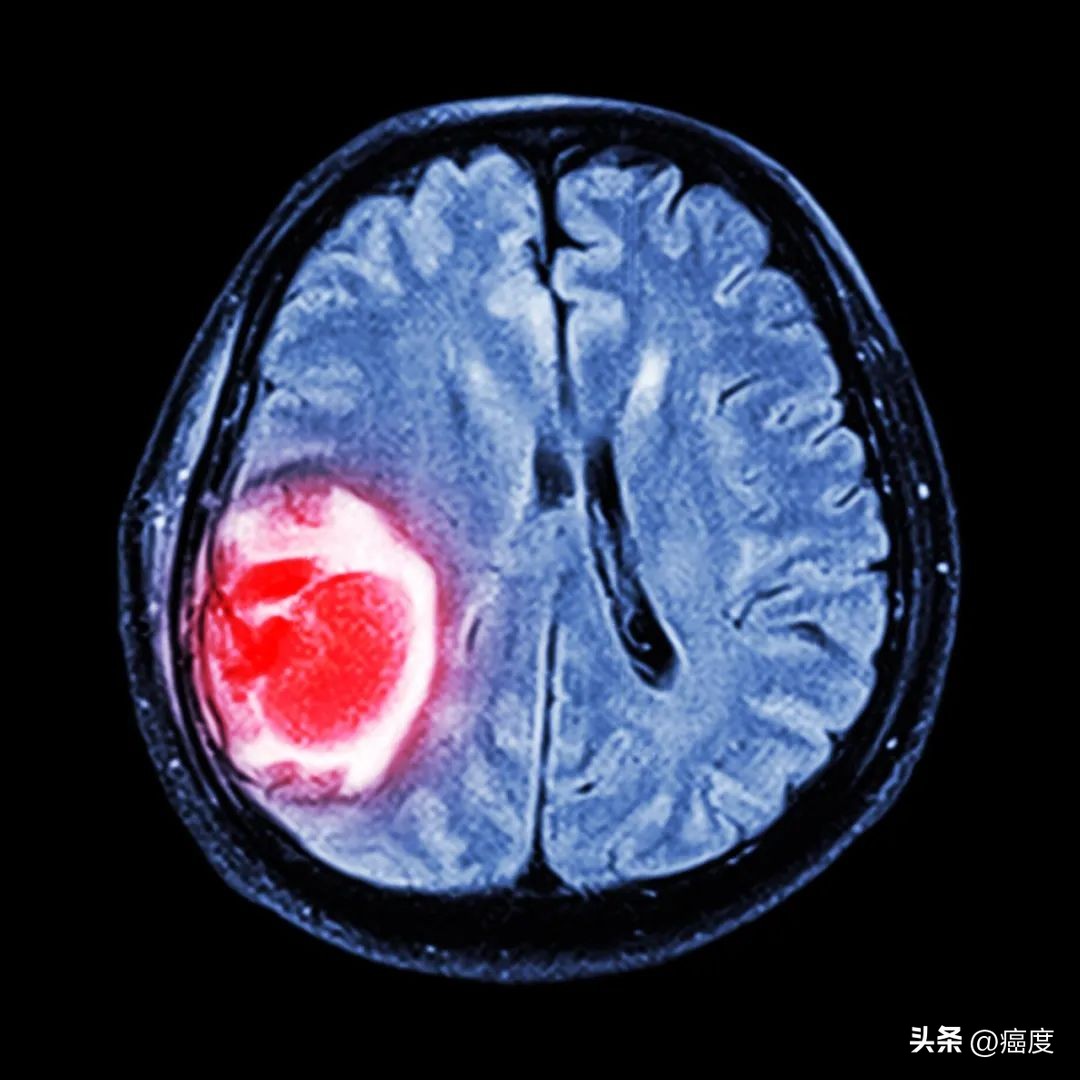

(图片来源:摄图网)